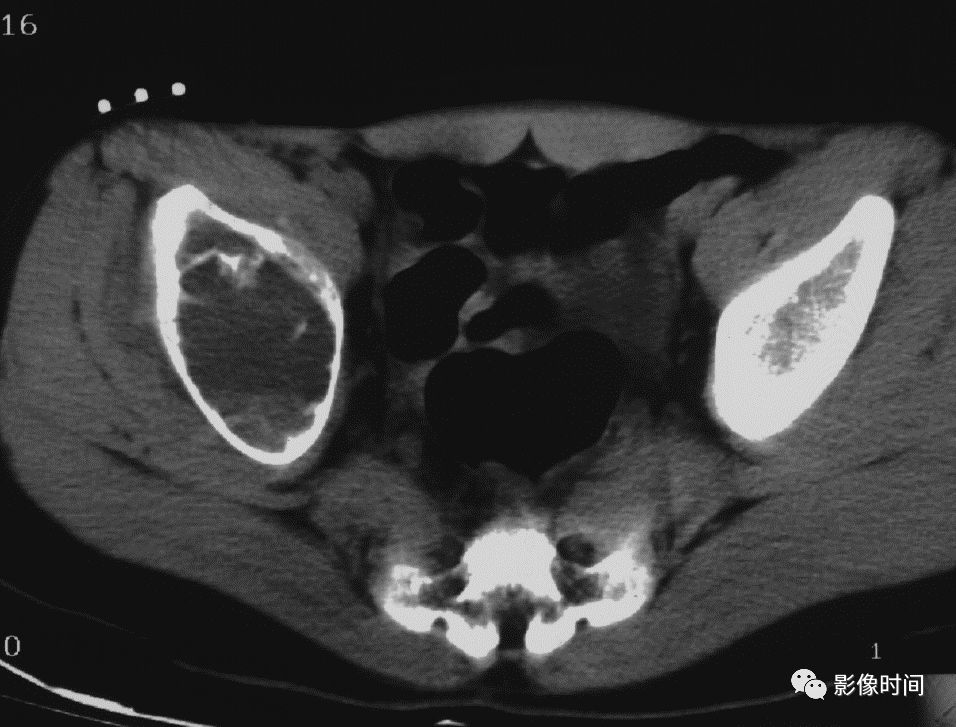

(一)瘤软骨钙化:瘤软骨常表现为环状钙化, 是诊断软骨类肿瘤较为可靠的影像学征象。环状钙化形成于环状软骨、以及软骨小叶边缘的软骨基质。钙质沉着可呈小点状、小条状、半环状或弧形;亦可浓密相连、重叠呈菜花状。钙化环的形态和密度可反映瘤组织分化程度, 通过观察钙化环的形态和密度,有助于良恶肿瘤的鉴别。

良性瘤软骨之瘤细胞分化好、生长缓慢、血供充分, 钙化环完整,密度高, 边缘清楚。良性软骨类肿瘤如骨软骨瘤(图 35)、软骨母细胞瘤(图 36)、内生软骨瘤(图 37)等均可于瘤组织内发生环形钙化。

恶性瘤软骨则呈密度淡薄, 边缘模糊的不规则钙化,恶性骨肿瘤的环形钙化,最多见于软骨肉瘤(图 38),其次是骨肉瘤。CT 是发现肿瘤内软骨钙化最为敏感的检查方法。

图 37  瘤软骨钙化:内生软骨瘤

图 38  瘤软骨钙化:软骨肉瘤